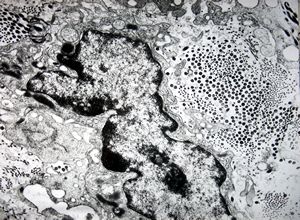

F, 46y. | verruca vulgaris … intranuclear virions

F, 46y. | verruca vulgaris … intranuclear virions

F, 46y. | verruca vulgaris … intranuclear virions